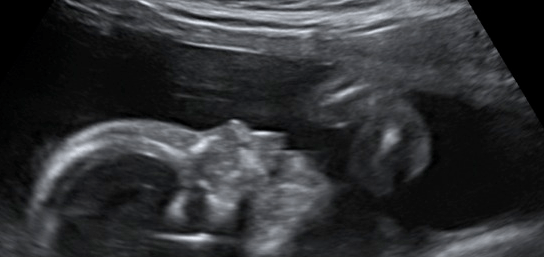

Our own research also supports a finding that breastfeeding increases IQ. We performed a prospective multicenter Australian study examining the association between breastfeeding and child IQ at 18 months. Expectant mothers were recruited from antenatal clinics between 12 and 20 weeks gestational age. Infants were subsequently followed to 18 months of age (12).